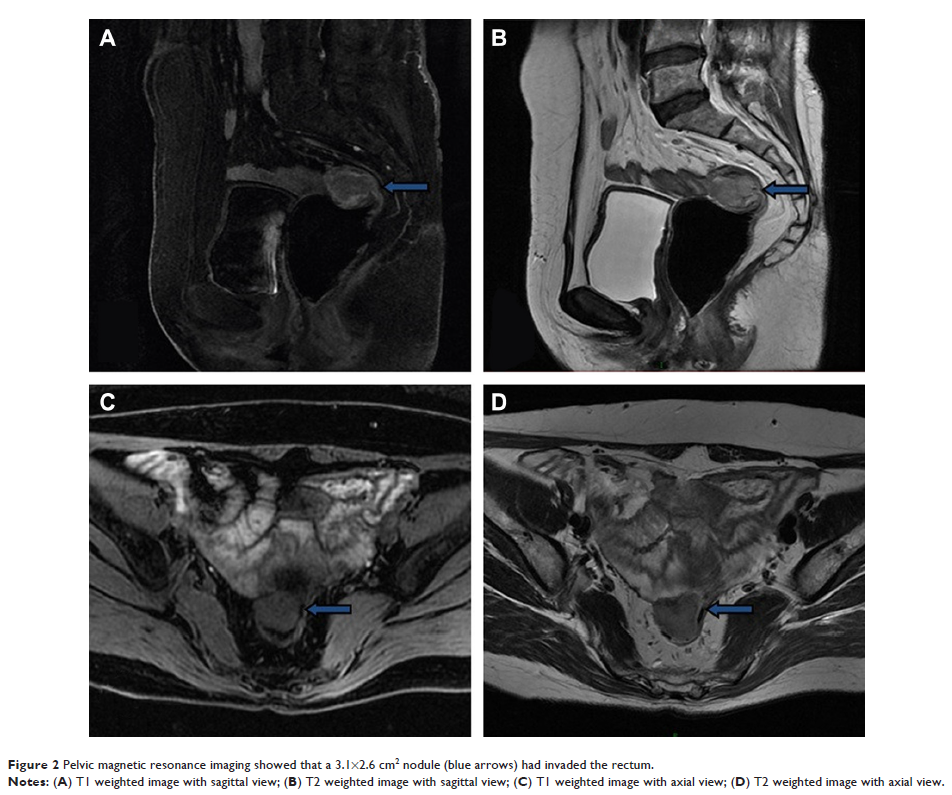

- 作者:Hao Su, Bin Li, Wenhao Ren, Mandula Bao, Peng Wang, Qian Liu, Xishan Wang, Zhixiang Zhou, Haitao Zhou